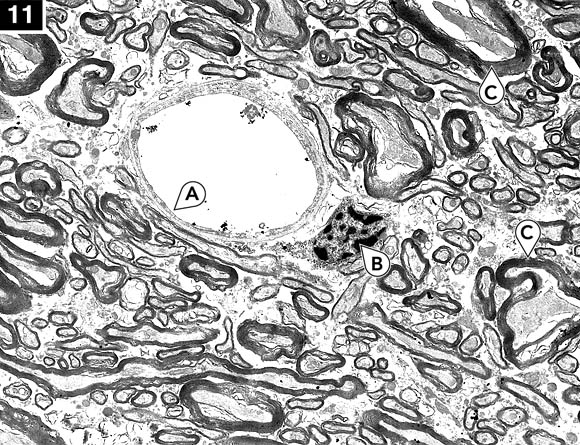

El glicerol a 70% w/v es casi incongelable. Esto significa que después de formar cavidades de hielo, más o menos dispersas, la solución concentrada restante se vitrifica (se solidifica sin congelarse) cuando se enfría por debajo de la "temperatura de transición vítrea". La mayor parte del tejido se solidifica en una matriz vítrea con un daño mínimo, tal y como se muestra en las micrografías siguientes:

Tejido cerebral congelado y descongelado utilizando glicerol: Típica apariencia de materia gris a 6700 aumentos. Nótense intactas las células endoteliales capilares (A) y las partículas de carbón (B) en el lumen capilar. La apariencia general del neuropil y de los axones y neuronas es excelente.

Tejido cerebral congelado y descongelado utilizando glicerol: La materia blanca del cuerpo calloso a 6700 aumentos. Nótese la excelente preservación de los capilares (A) y las membranas de plasma celular endotelial. El núcleo (B) muestra la típica perdida o reorganización del nucleoplasma; esto se ve con más frecuencia en cerebros congelados y descongelados que en cerebros sólo perfundidos con glicerol y fijados sin congelar. Varios axones (C) muestran el típico agrietamiento del axioplasma y alteración en la estructura de mielina. El incremento de espacio libre entre los axones y otras estructuras es el resultado de la deshidratación inducida por el glicerol.